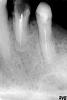

sergnew Опубликовано 8 сентября, 2012 Поделиться Опубликовано 8 сентября, 2012 Что делать с этими зубами? Ссылка на комментарий

Bobby Опубликовано 8 сентября, 2012 Поделиться Опубликовано 8 сентября, 2012 Можно попробовать их сохранить. Но этого снимка для диагностики не достаточно. Ссылка на комментарий